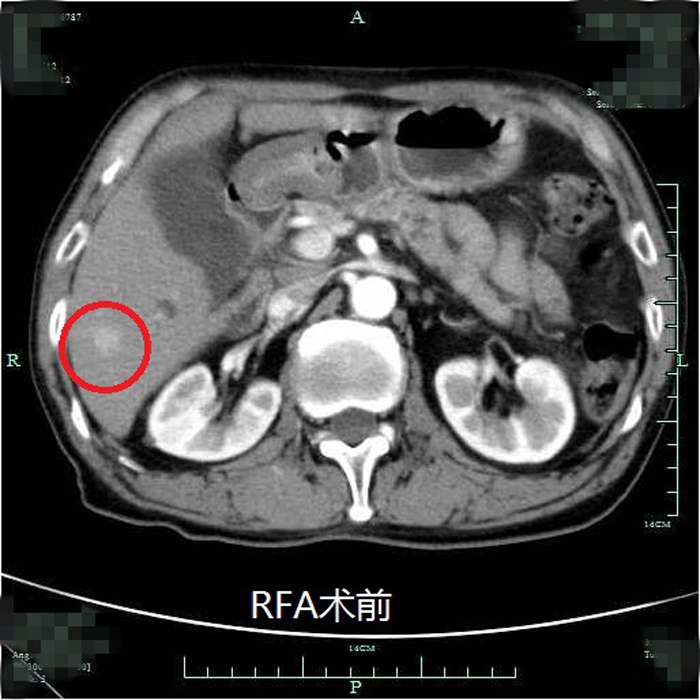

典型射頻治療患者術(shù)前術(shù)后效果對(duì)比(非該尾狀葉患者)

??? 近年來,我院肝膽外科在肝癌治療的綜合體系方面更加合理完善,肝癌射頻消融術(shù)已逐步成為繼肝癌切除術(shù)、經(jīng)皮選擇性肝動(dòng)脈栓塞化療(TACE)后常規(guī)開展的治療手段。自2012年開展此項(xiàng)技術(shù)以來,針對(duì)常規(guī)部位的肝癌射頻消融均取得了非常理想的效果。但由于尾狀葉腫瘤位置較深,周圍大血管包繞,不僅手術(shù)難度大,能否安全徹底地對(duì)該部位腫瘤進(jìn)行射頻消融也具有一定的挑戰(zhàn)性。此次在超聲影像等多學(xué)科的團(tuán)隊(duì)協(xié)作下,成功完成了尾狀葉腫瘤的射頻消融術(shù)。